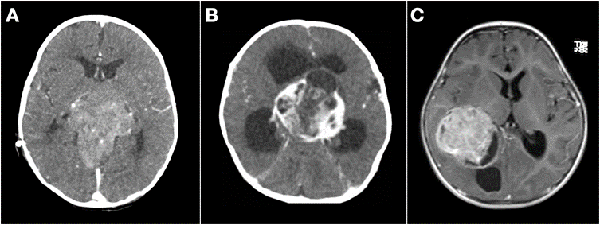

Se realizó biopsia en 3 lesiones de tronco cerebral, 1 lesión pineal abordada endoscópicamente, 1 lesión hipotalámico-quiasmática, 1 lesión frontal subcortical y 1 lesión centroencefálica extensa. En los dos últimos casos se efectuó sólo biopsia por el intenso sangrado que obligó a suspender el procedimiento. El diagnóstico histológico fue tumor embrionario en ambos, por lo que se trataron con quimioterapia (Figura 5-B).

Un tema controvertido es definir cuando un tumor de SNC es congénito. Solitare et al. 14 los divide en: "definitivamente congénitos" que son aquellos que producen síntomas al nacer, "cercanamente congénitos" que son los que producen síntomas dentro de la primera semana de vida, y "probablemente congénito" que son los que se manifiestan dentro del primer mes de vida. La inclusión de pacientes de hasta 2 meses de edad fue propuesta por Arnstein et al. 1 siendo este el límite más aceptado para definir el origen congénito. Sin embargo, hay otros autores como Jellinger y Manoranjan16,17 que extienden esta definición al primer año de vida. Con base en las definiciones de los últimos dos investigadores, nuestra serie presentó 26 casos menores de un año, de los cuales solo 3 fueron menores de 2 meses de vida, todos ellos tumores embrionarios (2 indiferenciados y 1 teratoma inmaduro) (Figuras 2 y 5 B).

Figura 5: Tumores agresivos. A) Paciente de 8 meses de vida, sexo masculino, presentó irritabilidad, macrocefalia y somnolencia. TC de cerebro con contraste EV donde se observó imagen en región pineal que se extiende al tercer ventrículo. Se realizó cirugía de exploración, exéresis parcial, anatomía patológica informó pineoblastoma, paciente falleció a los 5 meses por progresión de la enfermedad. B) Paciente de 2 meses de vida, sexo masculino, consultó por deterioro progresivo del sensorio. TC de cerebro con contraste EV que evidenció lesión centroencefálica e hidrocefalia obstructiva. Se realizó cirugía de exploración de lesión, con colocación intraquirúrgica de drenaje ventricular al exterior. Anatomía patológica informó tumor embrionario indiferenciado. Paciente falleció a los 14 días por progresión de enfermedad. C) Paciente de 19 meses de vida, sexo femenino, consultó por vómitos a repetición. IRM de cerebro con contraste EV que mostró tumor supratentorial intraventricular con realce homogéneo con el contraste EV. Se realizó cirugía de exploración, con exéresis parcial por el intenso sangrado. Anatomía patológica informó carcinoma de plexos coroideos. Paciente fallece a los 3 meses.